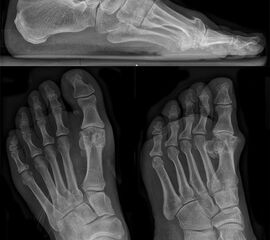

• Röntgen: Fuß belastet in 3 Ebenen.

• Optional MRT und CT bei radiologisch unklaren Verhältnissen.

Zum Lesen der Bildbeschreibung und zur Vollansicht bitte das Bild anklicken (Foto: M. Walther).